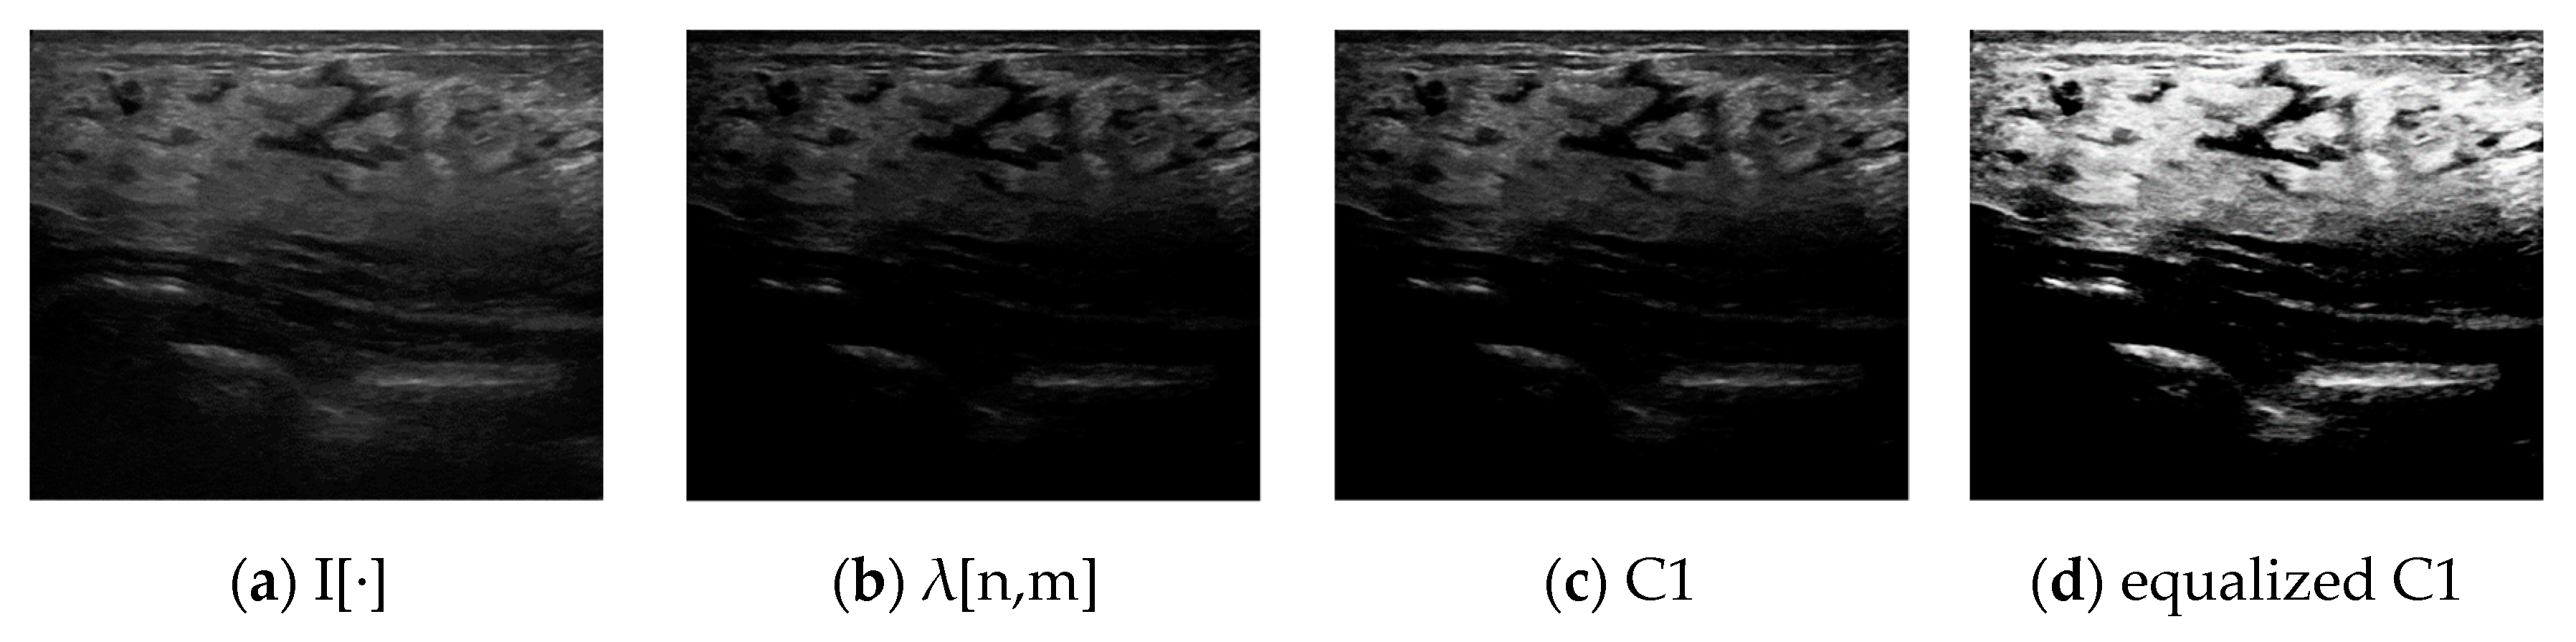

3.1.3. Noise Reduction and Channel Expansion through Histogram Equalization